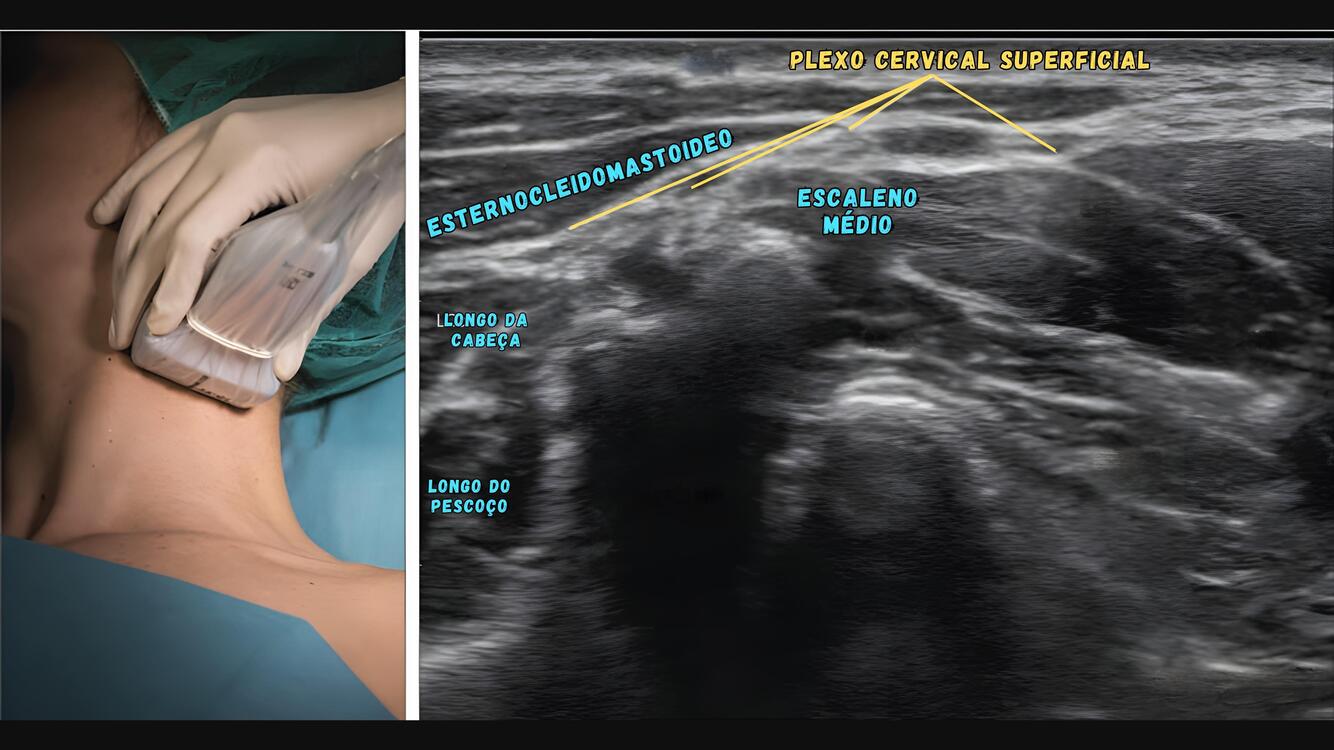

Os ramos do plexo cervical superficial emergem da borda:

A

Posterior do ECM

O plexo cervical superficial é formado por raízes que saem de C1 a C5, emergindo na região cervical lateral, na altura do processo transverso de C4, junto à borda posterior do esternocleidomastóideo.

Bloqueio muito interessante em cirurgias de ombro e fundamental para cirurgias abertas de carótida, onde o paciente idealmente precisa estar consciente e colaborativo.

O plexo cervical superficial compreende quatro nervos (**___1___**) e pode ser localizado posterolateralmente ao **___2___** ao nível da cartilagem **___3___**.

1. supraclavicular, cervical transversal, auricular maior e occipital menor 2. esternocleidomastóideo 3. cricoide

O plexo cervical superficial é bloqueado no **___1___** do bordo posterior do músculo **___2___**.

1. ponto médio 2. esternocleidomastóideo